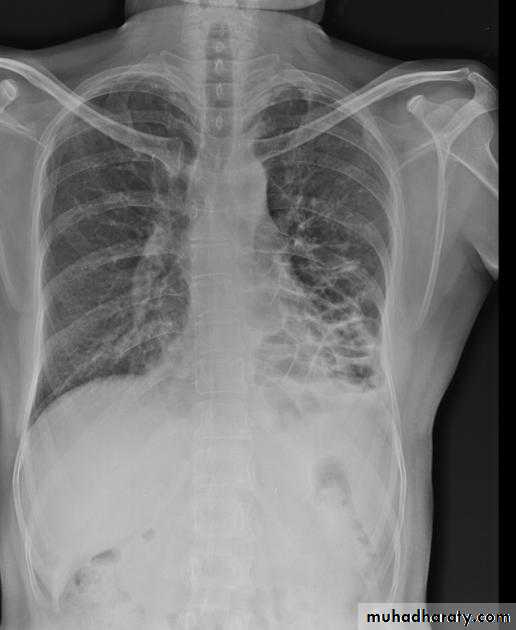

Miliary TB

65.Miliary TB

66. miliary TB